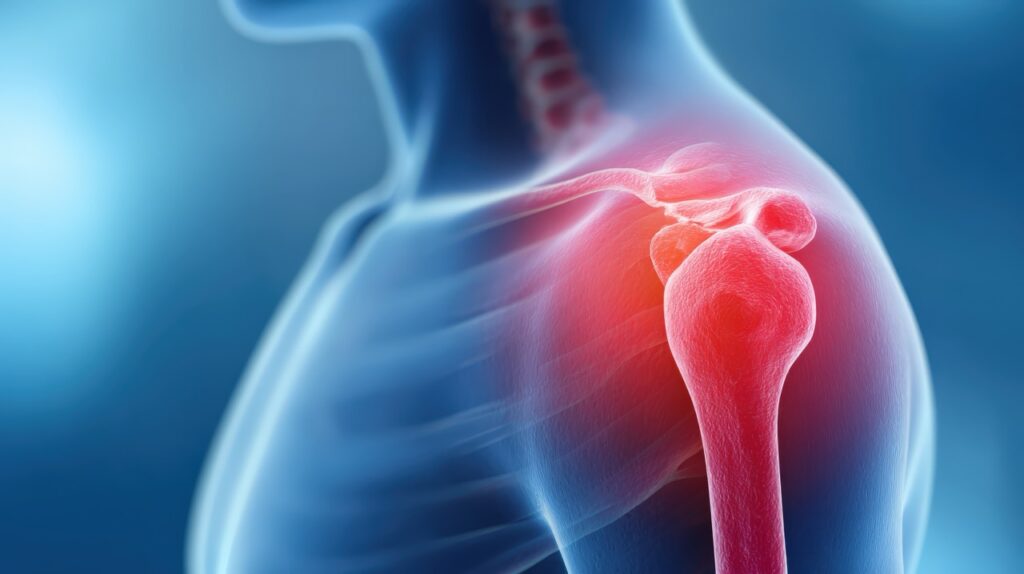

What Should I Expect During a Shoulder MRI in Cypress Creek?

Shoulder MRI Cypress Creek: What Happens Before, During, and After Your Scan Shoulder pain can make simple tasks feel impossible. Reaching for items, lifting bags, or even sleeping comfortably becomes a challenge. When shoulder problems persist, your doctor might recommend an MRI to identify the cause. At Precision MRI Group, we understand that shoulder MRI […]

Shoulder MRI Cypress Creek: Diagnose Pain, Rotator Cuff Tears

Shoulder MRI Cypress Creek: Identify Pain, Rotator Cuff Tear Causes and Injuries Shoulder pain can affect daily activities, from lifting groceries to playing sports. When discomfort continues, finding the cause is important. A shoulder MRI Cypress Creek gives doctors the detailed images they need to understand what is happening inside your shoulder. This type of […]